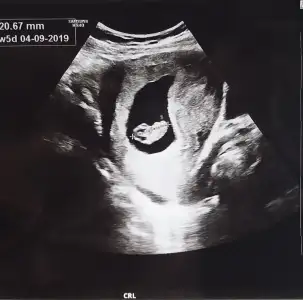

Merhaba; bir ultrason kağıdı 6 haftalık diğer ikili olan 9 haftalık resimler benim bebeğimin cinsiyeti tahminen sizce nedir arkadaşlar ?

Tecrübeli arkadaşlardan tahminler alabilirmiyim?

Eklentiler

• FCE180CD-1078-4D38-B11C-54F7331E4B56.webp

FCE180CD-1078-4D38-B11C-54F7331E4B56.webp